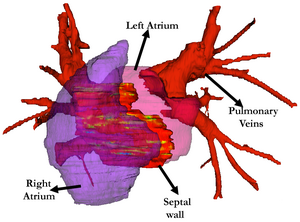

- 7.13 Optimal Transseptal Puncture Location for Robot-assisted Left Atrial Catheter Ablation